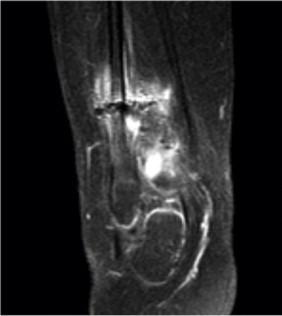

Serratia marcescens is an unexpected pathogen for subacute osteomyelitis in adolescence. Because of difficulty of diagnosis, treatment can be delayed or cause complications like nonunion or loss of function. We present a meningomyelocele female adolescent operated with distal tibia varus osteotomy for correcting ankle valgus deformity. Insufficient healing was determined at osteotomy side on radiographs. The patient's erythrocyte sedimentation rate and CRP level was slightly higher with minimal clinical inflammation. MRI examination showed abscess formation at T2 imaging. Debridement, grafting and circular external fixation was performed. Sulperazon was started for drug therapy. Union was achieved after compression and distraction osteogenesis by circular external fixator. Orthopedic surgeons should be aware of opportunistic infections like serratia and keep in mind as a probable cause of disease.

粘质沙雷氏菌是青少年亚急性骨髓炎中一种意想不到的病原体。由于诊断困难,治疗可能会延迟或导致诸如骨不连或功能丧失等并发症。我们报告一名患有脊髓脊膜膨出的女性青少年,她接受了胫骨远端内翻截骨术以纠正踝外翻畸形。X线片显示截骨部位愈合不佳。患者的红细胞沉降率和CRP水平略有升高,临床炎症轻微。MRI检查在T2成像上显示有脓肿形成。进行了清创、植骨和环形外固定。开始使用舒普深进行药物治疗。通过环形外固定器进行加压和牵张成骨后实现了骨愈合。骨科医生应意识到像粘质沙雷氏菌这样的机会性感染,并将其作为可能的病因牢记在心。